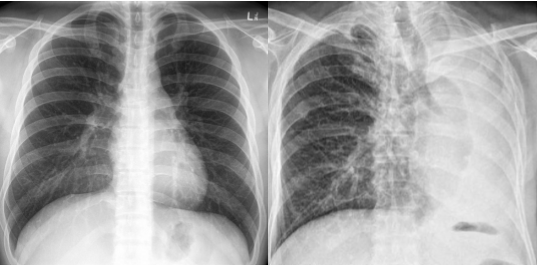

Differentiate which is PA vs AP view. Why

Left PA:

clavicles ELEVATED

medial border of scap NOT in center of lung fields

heart NOT magnified and enlarged

Right: AP

clavicles HORIZONTAL

scapulae in lung fields

heart appears magnified/elarged

labeled PA view